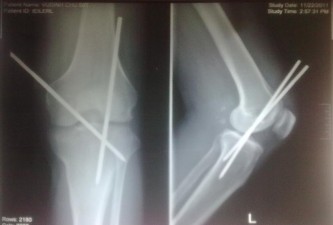

• Sai khớp gối: cố định khớp gối bằng xuyên đinh Steinmann 4 mm x 20 mm (ảnh 2.3) hoặc cố định ngoài. Tư thế cố định khớp gối gấp 150 nếu ghép mạch hoặc 300 nếu khâu nối mạch.

Ảnh 2.3: Hình ảnh XQ cố định khớp gối bằng đinh Steinmann

(Bệnh nhân Vũ Đình Ch., 59 tuổi. Số BALT: 2042)